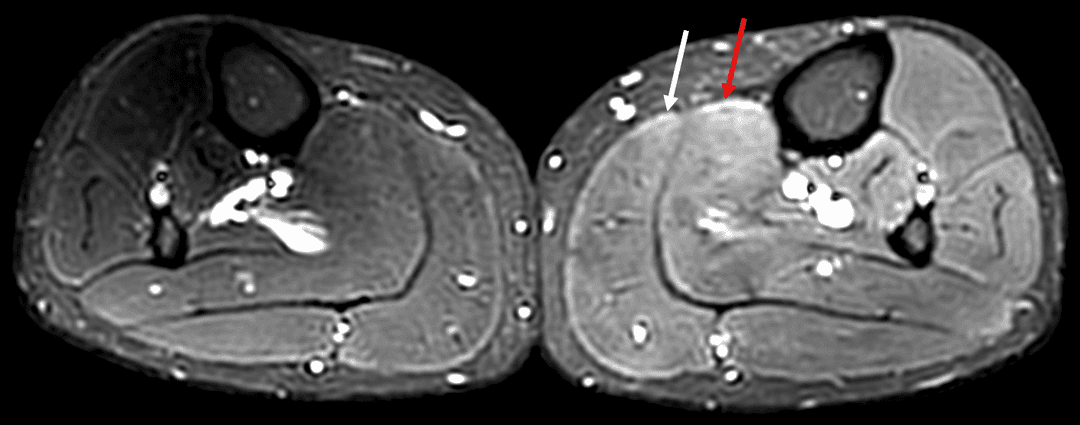

Œdème musculaire mal systématisé apparaissant en hypersignal T2 FS modéré au sein des muscles soléaire (flèche rouge) et gastrocnémien médial (flèche blanche) du mollet gauche, associé à une majoration modérée du volume de ces deux muscles comparativement au côté droit.

Axial T2 FS